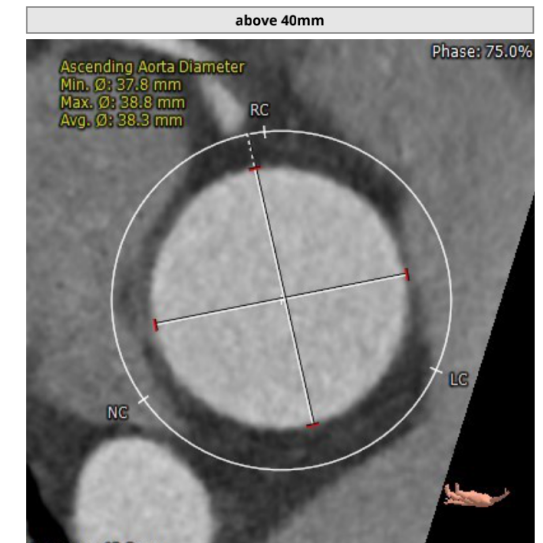

升主动脉直径:38.3mm,心脏夹角:48度